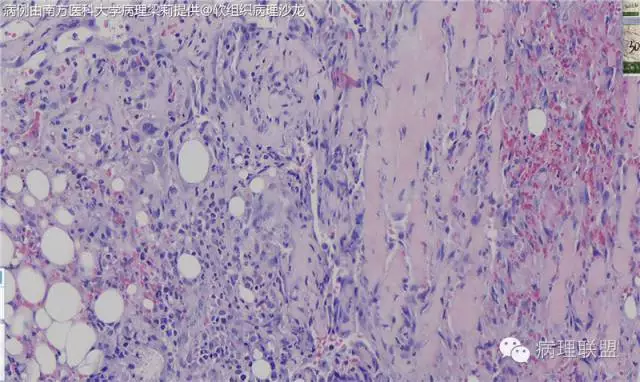

新生儿,男,14天。生后发现右前臂暗红色肿物14天。术中见:肿物2x1.5cm,深达筋膜下及肌膜表面,暗红色血管样。(南方医科大学病理梁莉提供 致谢!)

这例我们发的是卡波西样血管内皮细胞瘤,考虑如下:(1)新生儿,肢体肿物;(2)位置深,侵及皮下脂肪;(3)大多是裂隙状血管,也有少量吻合的血管网,细胞有异形,可见坏死

而复合性血管内皮瘤则是由良性、中间性和恶性的成份组成,也是浸润性生长,常常侵犯皮下脂肪组织,此例细胞形态由梭形细胞、卵圆形细胞及上皮样细胞组成,形态可见良性区域、中间性区域及高分化血管肉瘤或上皮样血管肉瘤区域,因此,似乎复合性血管内皮瘤更妥。此类肿瘤可以发生于婴幼儿。当然与Kaposi型血管内皮瘤一样,同属中间性血管瘤,只是后者,若肿瘤体积大,可出现Kasabach-Merritt综合征。

@南方医科大学病理梁莉 一样,若肿瘤体积大,可出现Kasabach-Merritt综合征。则因消耗血小板,预后就差多了。